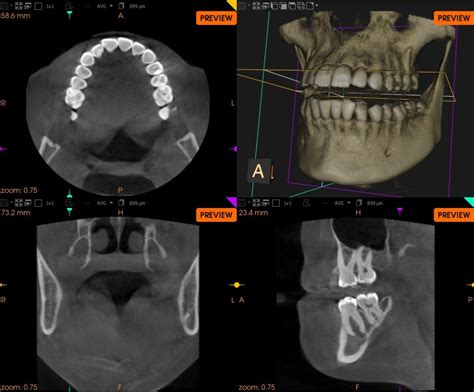

Cone Beam Computed Tomography (CBCT)

CBCT is an advanced imaging technology that produces 3D images of the teeth, jaws, and surrounding structures. This detailed view allows for precise diagnosis and treatment planning for:

• Dental implant placement.

• Complex root canal treatments.

• Orthodontic evaluations.

• TMJ (temporomandibular joint) disorders.

• Surgical planning and assessment.